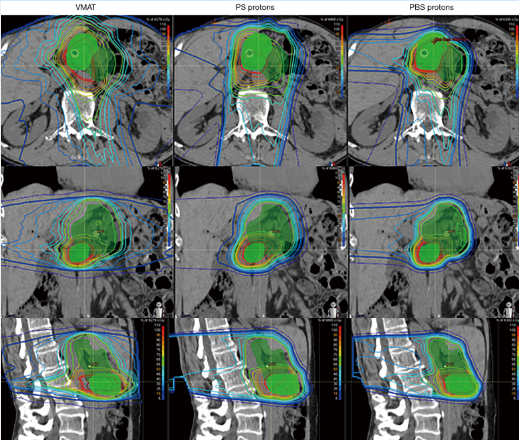

▲传统放疗、被动散射质子治疗和 (PS) 和笔形束扫描质子治疗 (PBS) 胰腺癌的剂量分布图,图源:参考来源[10]